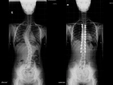

Skolyozun tanısı genellikle fizik muayene ve görüntüleme yöntemleri ile konulur.

• Fizik muayene sırasında doktor, omurganın görünümünü değerlendirir ve belirtileri inceler.

• X-ray, skolyozun derecesini belirlemek için en yaygın kullanılan görüntüleme yöntemidir.

• Gerekirse, MRI veya CT taramaları ile daha detaylı bilgi edinilebilir.

Bu yöntemler, skolyozun ciddiyetini ve tedavi gereksinimlerini belirlemede kritik öneme sahiptir.